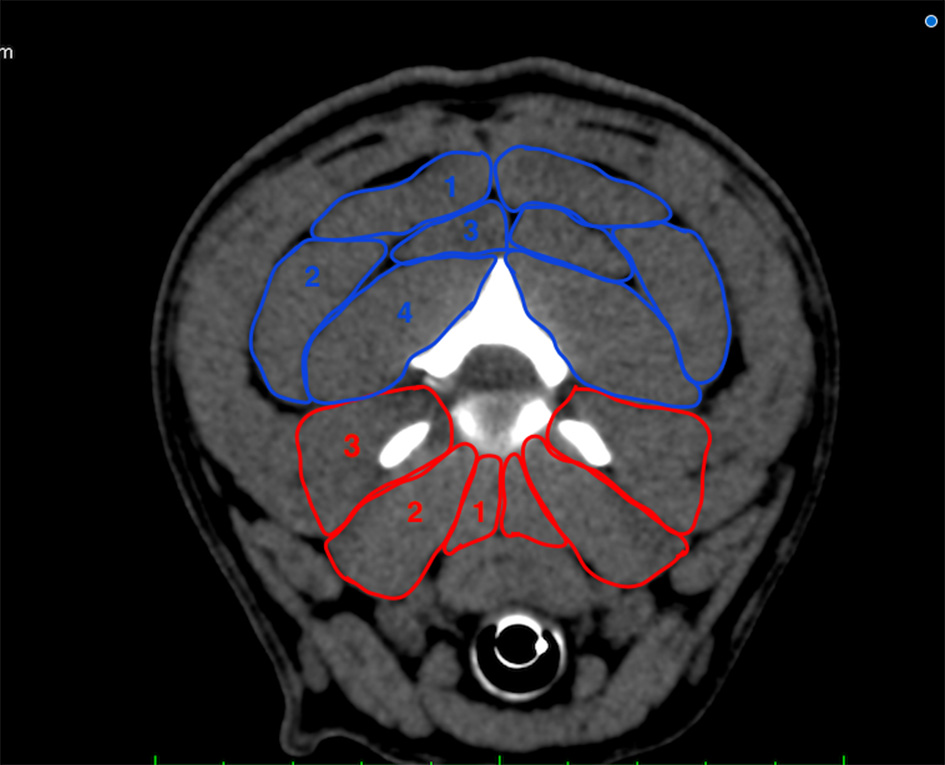

Figure 1

Transverse plane depiction of the paraspinal muscles included in the measurement at the level of C2/C3. Dorsal group (blue): M. biventer cervicis (1), M. longissimus atlantis et capitis (2), M. complexus (3), M. obliquus capitis caudalis (4); ventral group (red): Mm. intertransversarii (3), M. longus capitis (2), M. longus colli (1).